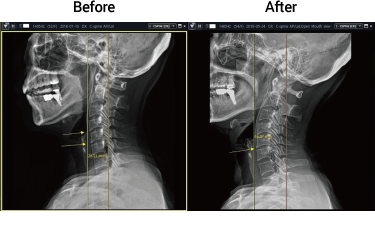

일자목

50대 여성